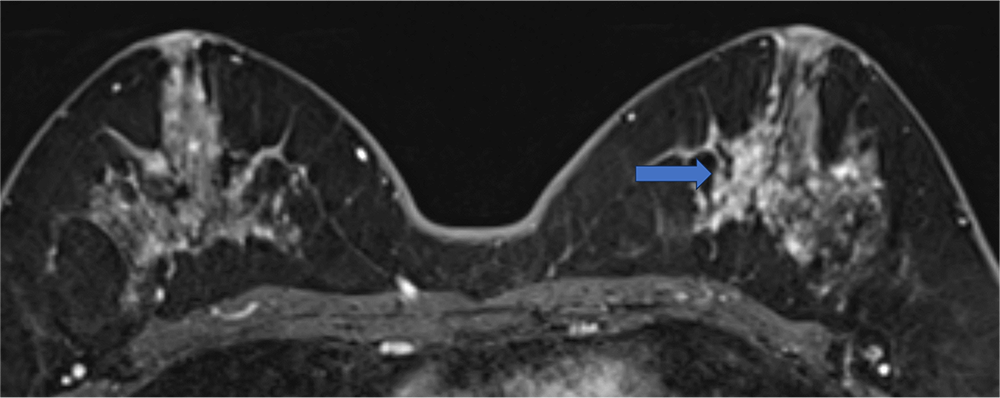

4. ダイナミックMRI 造影前 早期相 遅延相

左乳房内側にやや増強効果が目立つ領域があるがBPEも強いため同定が困難である。

ダイナミックMRI 早期相

ダイナミックMRI 遅延相